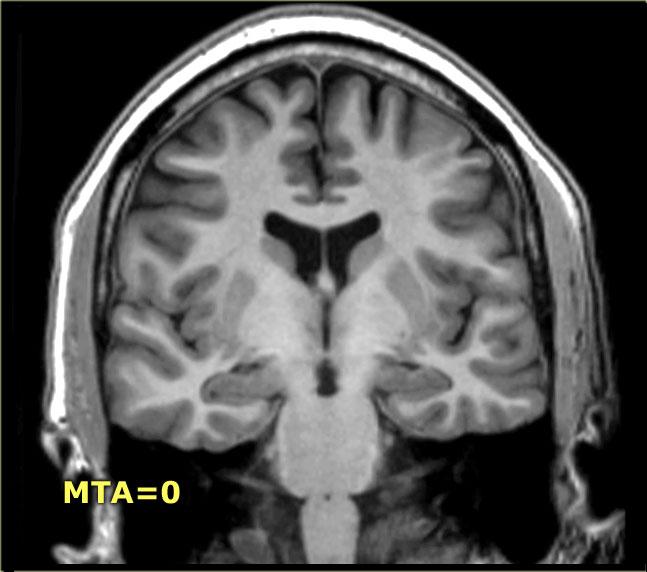

Điểm MTA cần được đánh giá trên chuỗi xung T1W mặt phẳng coronal tại một vị trí lát cắt nhất quán.

Chọn lát cắt qua thân hồi hải mã, ở mức cầu não trước.

Điểm số được tính dựa trên đánh giá trực quan chiều rộng của khe mạch mạc, chiều rộng của sừng thái dương và chiều cao của cấu trúc hồi hải mã.

- Điểm 0: Không có teo não

< 75 tuổi: Điểm từ 2 trở lên là bất thường.

> 75 tuổi: Điểm từ 3 trở lên là bất thường.